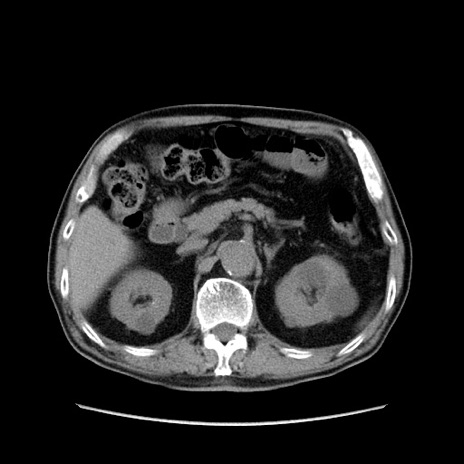

症例24(横断像)

【症例】80歳代男性

【主訴】左側腹部痛、嘔吐

【現病歴】本日早朝より左腹部に痛みあり。昼頃嘔吐認めたため、救急要請。

【既往歴】直腸癌(Mile手術)、胆摘

【身体所見】意識清明、BT 35.9℃、BP 221/93mmHg、SpO2 97%(RA) 、腹部:左ストーマ周囲に限局性の腹部膨隆あり。 膨隆部自発痛・圧痛あり・軟。

【データ】WBC 7700、CRP 0.09